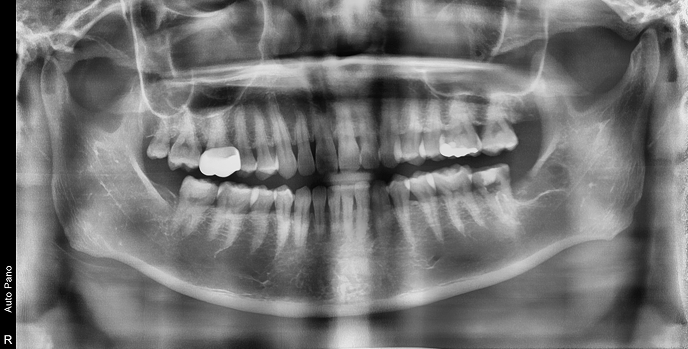

• 20대 남성 | #38 사랑니발치 | 치료기간 당일

Before 2022.06.24

After 2022.06.24